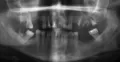

Хочу вставить два зуба. А врач-протезист отказывается поставить постоянные зубы. Предлагает съёмный протез. Объясняет, что надо будет точить соседние зубы. Если даже вставить постоянные, то два зуба будут белые, а два — жёлтые.

Вопрос: бывает ли другой способ (наращивание зуба или имплант)?

Все зависит от нескольких факторов. Для имплантации необходим качественный объём кости, которого, скорее всего, нет. Для протезирования необходим факт устойчивости зубов.

Протезирование съёмным протезом при отсутствии всех вышеперечисленных аномалий — самый простой и бюджетный выход.